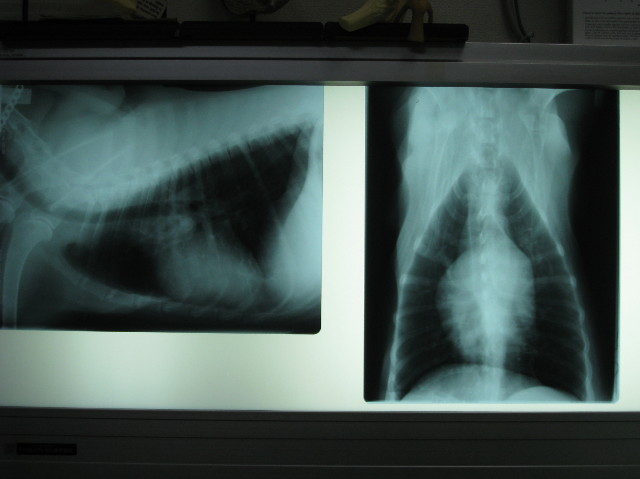

ちなみにこちらは【2008年3月16日】のレントゲン。

1年前はほとんど石灰化が見られないよね。

....約1年でこんなにかわっちゃうんだね。。。